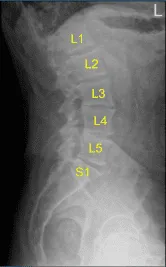

El paciente está en estado tras una hemilaminectomía y microdiscectomía en L2-L3 por una compresión de la raíz nerviosa L3 derecha realizada hace dos semanas. El paciente estaba bien en la postoperatoria. Su dolor se resolvió. Podían realizar las actividades habituales de la vida diaria. Estaban teniendo algo de estreñimiento. También hicieron algunos trabajos en el jardín.

Se realizó una descompresión adicional de la laminotomía con la exposición. También se realizó una foraminotomía de la raíz nerviosa L3. La fuga de LCR se encontró en la superficie dorsal. Medía unos 5 mm de largo. Estaba lleno con hamburguesas y luego Surgicel.

La descompresión de revisión se completó retirando la lámina superior de L3, medial, lateral e inferior L2 usando el punzón de Kerrison nº 3. La faceta inferior de la vértebra L2 en el lado derecho estaba suelta y tuvo que ser extirpada. Tras una descompresión exhaustiva, se planificó la reparación de la durotomía incidental.